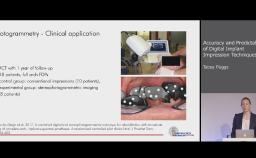

Dental implants are designed to provide support, stability, and retention for dental prostheses. In addition, implants have evolved to enable optimal esthetic and functional outcomes for patients seeking dental rehabilitation for a variety of indications. This lecture focuses on optimizing prosthodontic outcomes for patients via a systematic and evidence-based team approach to treatment. This includes contemporary treatment planning with an emphasis on communication of ideal implant placement; choice of implants, components, and restorative biomaterials to minimize complications; and prosthesis design and maintenance options to enhance longevity.

- apply contemporary evidence-based prosthodontic protocols to comprehensive treatment strategies for a range of partially and completely edentulous indications